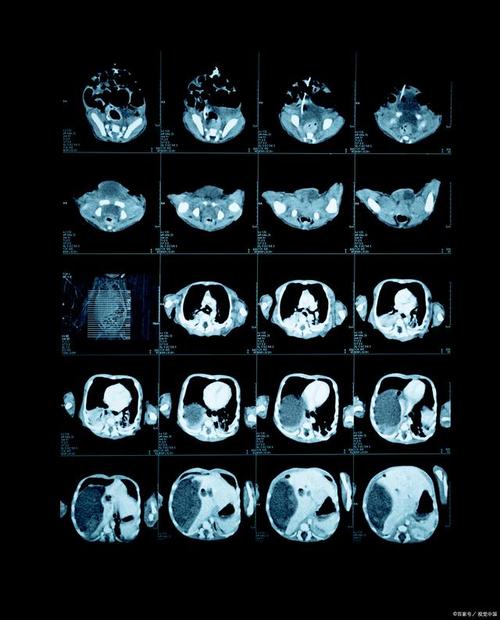

| CT | 肺癌(肺结节检测与良恶性判断)、脑卒中(出血/缺血)、冠状动脉钙化评分、肝脏/胰腺肿瘤 | 精准分割病灶(圈出病变范围)、量化分析(如结节体积、密度变化)、预测良恶性,辅助制定手术方案。 |

(图片来源网络,侵删)- 快速筛查:AI可以在几秒钟内完成对一张影像的初步分析,标记出可疑区域,帮助医生从海量影像中快速“挑出”重点,大大缩短了阅片时间。